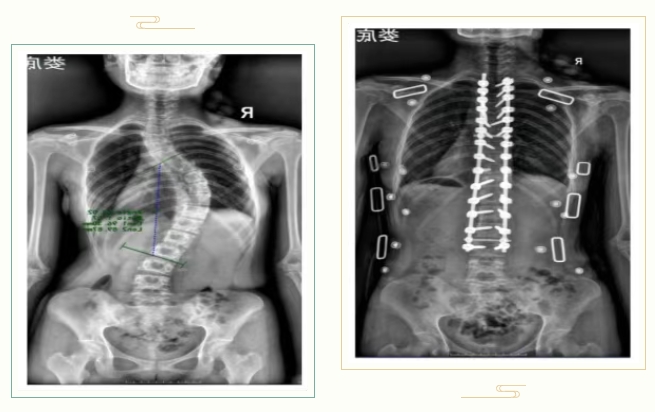

(3)>40度:椎弓根螺钉矫正术

手术如同在脊柱上架起“钢轨”,矫正率可达70%